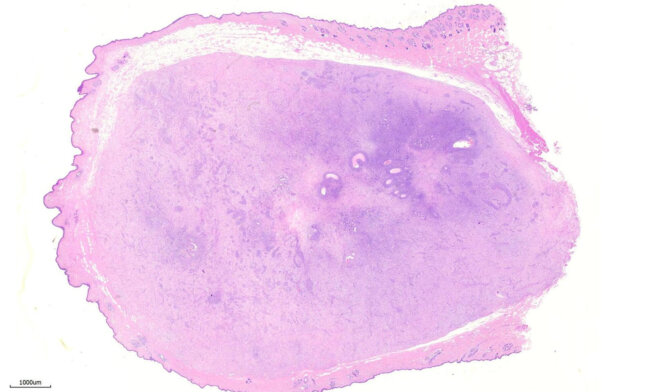

動物外科病理-腫瘤淋巴結轉移

腫瘤轉移-腎臟 Tumor renal metastases